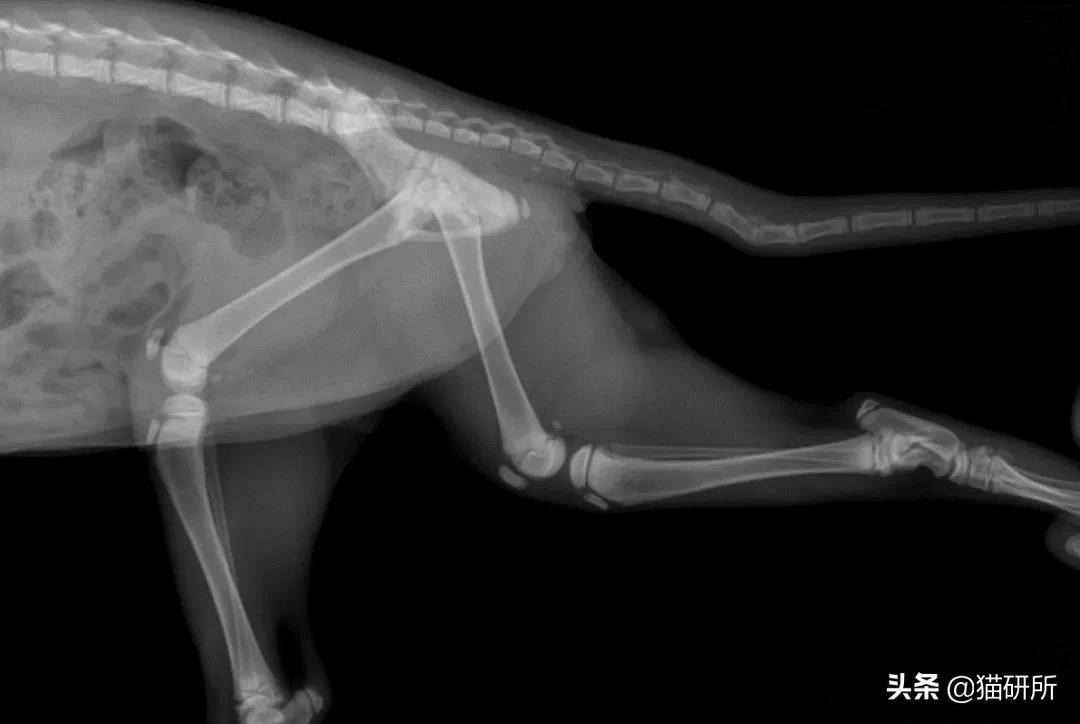

四肢骨骨折

最常见的骨折。绝大部分由外伤(不合理的运动,冲撞,跌倒等)导致。6个月以下或肥胖的猫更为常见。

猫四肢骨骨折 图自:猫研所动物医院